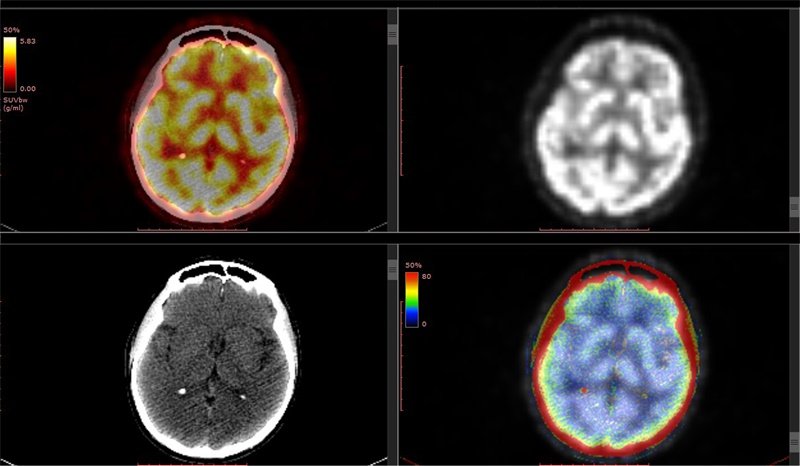

影像一出来,报告上写着"疑似肿瘤进展"。患者和家属的天塌了,...

更新时间:2026-04-09 11:09:13

影像上"变大"并不等于肿瘤真的复发了。有一种叫做"假性进展"的...

更新时间:2026-03-31 10:30:13